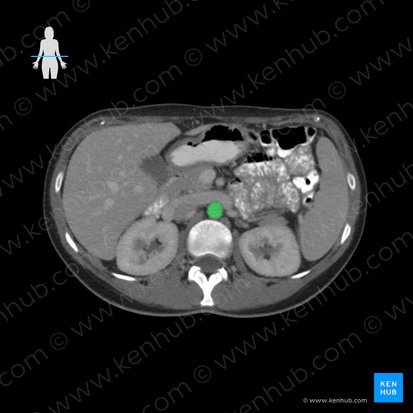

Schließlich sollten auf dem CT auch immer die großen Blutgefäße des Abdomens beurteilt werden. Zu diesen gehören die Aorta abdominalis und die Vena cava inferior. Die Aorta abdomianlis verläuft im Retroperitonealraum. Sie tritt durch den Hiatus aorticus des Zwerchfells (Th12) hindurch und steigt anterior der Wirbelsäule ab. Die Aorta abdominalis teilt sich auf Höhe des Vierten Lendenwirbels in zwei Endäste – die rechte und die linke Arteria iliaca communis. Die Vena cava inferior befindet sich rechts der Aorta. Sie entsteht durch die Vereinigung der beiden Vv. Iliacae communes auf Höhe des Fünften Lendenwirbels und tritt durch das Foramen venae cavae des Zwerchfells (T8) hindurch.